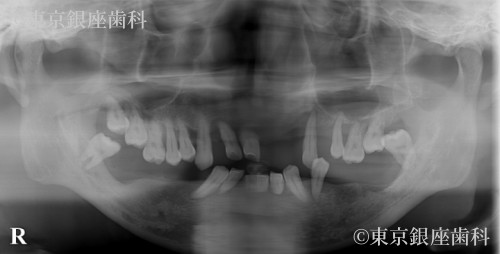

若年性の重度歯周病により早期から噛めない状態だった40歳代男性のインプラント治療症例

Before

進行の早い歯周病で強い不安を抱き来院。オペを決断しケアに前向きになったことで改善。途中破損・再手術を経たが最終的に安定した。